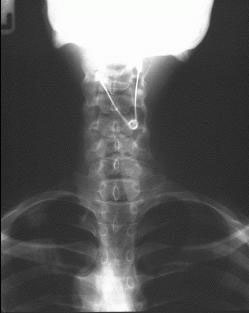

ez télleg nem vicces , egyik osztálytársam is lenyelt egy ilyet , és azóta se jött ki